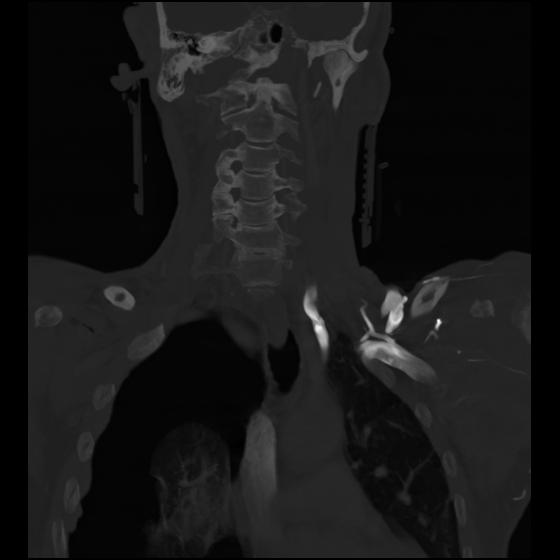

23 ANGIO,CE,Cor-MIP,5.000,ANGIO,Cor-MIP,